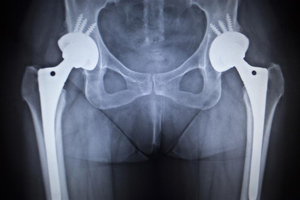

Hip replacement is a surgical procedure in which the damaged hip joint is replaced with a prosthetic implant. X-ray guided hip replacement involves the use of pre-operative radiographic studies to help select the right size of the implant and to determine the proper position in which the implant should be placed.

- Multiple X-rays will be taken to measure the length and depth of the damaged joint.

- The X-rays help in the selection and sizing of the implants based on your anatomy and can be used to identify anatomical landmarks that serve as reference points so that the prosthesis is implanted in the correct position.

- Special surgical instruments are introduced into the hip and based on the anatomic landmarks identified on the X-rays, the damaged tissue is removed and your surgeon will make precise cuts in your bone to place the implant components in the desired position.